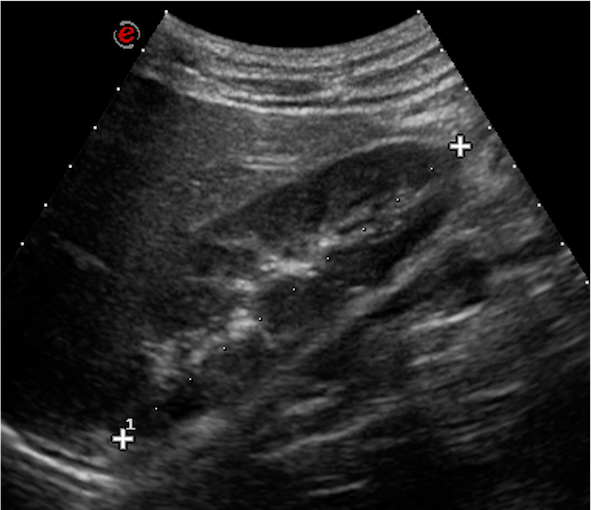

Dopo tre mesi il ragazzo ritorna presso il nostro ambulatorio: la proteinuria appare in netto peggioramento (1344 mg/24h), sempre accompagnata da microematuria, mentre si esclude una proteinuria ortostatica. Gli esami ematochimici eseguiti, comprensivi di emocromo, funzionalità renale ed epatica, assetto lipidico e proteico, complemento, indici di flogosi e autoanticorpi (ANA, anti-dsDNA, ANCA), risultano tutti nella norma. All’ecografia dell’addome confermati spot iperecogeni bilaterali come da nefrocalcinosi (Figura 1).